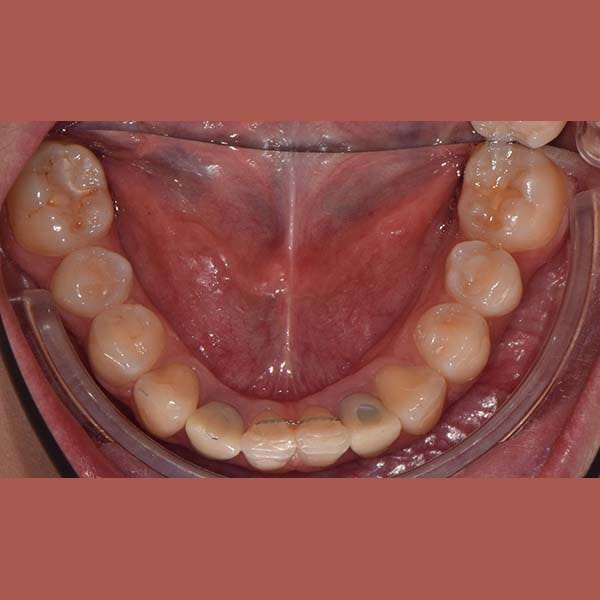

عانت هذه السيدة من وجود عضة عميقة أمامية و غياب خلقي لسنين أماميين سفليين ،بالإضافة لتراكب و عدم ارتصاف الأسنان الأمامية العلوية بشكل جيد – تم فتح مسافة كافية لوضع غرستين سنيتين و تم تصخيح العضة العميقة تقويمياً